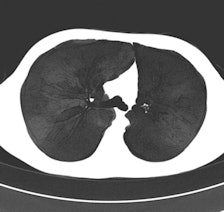

"The dilemma is: Do we opt for smaller radiation dose or fuller information?" asked Dr. Helmut Prosch, lead author of the survey presented at the European Respiratory Society Annual Congress in Vienna earlier this month. "The survey concluded that most radiologists prefer to obtain volume datasets and reconstruct them in different dimensions for additional information. Such reconstructions of volume datasets can be coronal or sagittal displays, maximal intensity projections, which are not high resolution but provide information on the distribution of nodules, or minimum intensity projections, which show the distribution and extent of emphysema or the details of an enlarged bronchi."

A number of potential protocols can be used to evaluate interstitial lung diseases with CT. The two main methods are discontinuous HRCT using 1-mm-thick slices with an intersection gap of 10 to 20 mm and volume CT. Compared with volume CT scans, discontinuous HRCT scans show only 10% of all information.